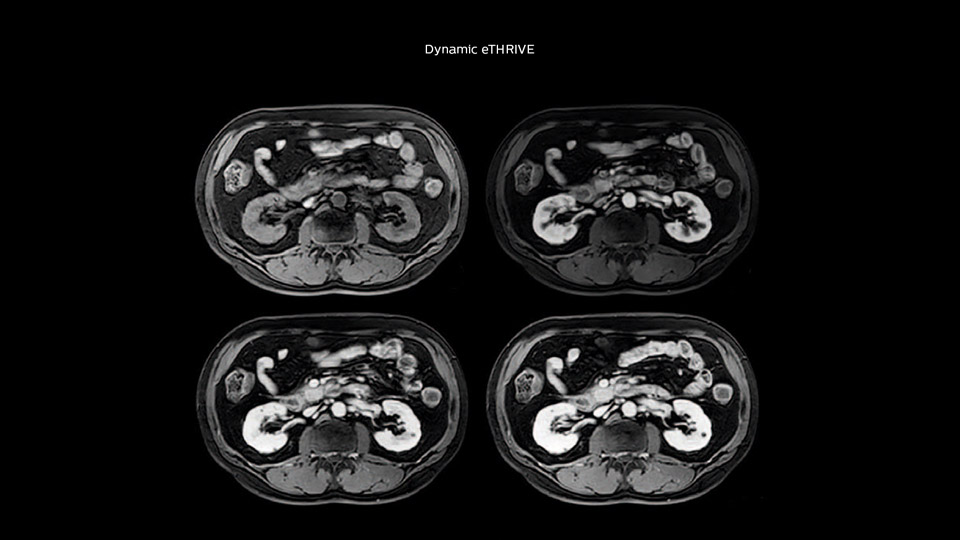

“We acquire one transversal high resolution T2-weighted sequence with 3 mm slice thickness, for example for pancreas or liver lesions. Then we also add a T2 fat suppressed MultiVane XD SPIR sequence. We perform these two routinely in our liver imaging. We use high dS SENSE factors to significantly shorten scan times to 2-4 minutes, which can improve our protocol; it’s a very robust scan.”

“We include mDIXON for the dynamic sequences because of the robust and homogeneous fat suppression we get with that. We had been using eTHRIVE, but we are now quite happy with mDIXON. Sometimes we use a medication to calm the bowels, to further improve the image quality.”